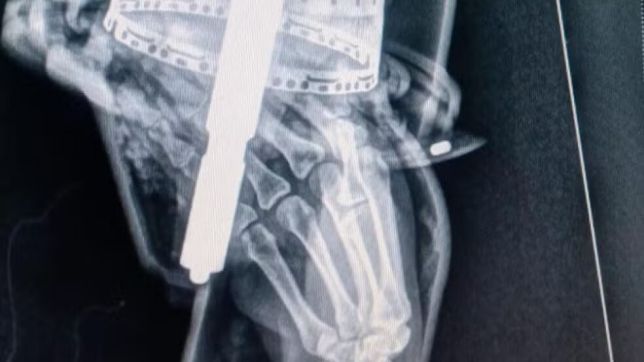

Uma mulher de 20 anos ficou com o antebraço preso em um multiprocessador e precisou ser socorrida pelo Corpo de Bombeiros, em Conselheiro Lafaiete, na Região Central de Minas Gerais, na tarde deste sábado (20).

Segundo a corporação, a vítima estava sentindo muita dor e foi levada com o equipamento ainda preso no braço para o hospital, para que fosse sedada.

Os bombeiros fizeram a retirada do multiprocessador, e um primeiro exame de raio-x não indicou fratura e outras lesões.